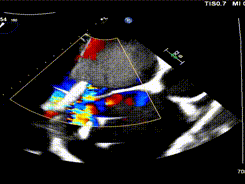

2区带彩

怎么上穿刺鞘攻克巨大左房伴转位穿刺难关!温医大附一院周浩教授团队创新应用“导丝定位+可调弯鞘”技术完成高难度TEER手术_https://www.jmylbn.com_新闻资讯_第6张

1.二尖瓣重度关闭不全(4+),瓣环明显扩大(AP径4.6cm,LM径3.9cm),扁平,关闭时瓣叶对合不佳(carpentier I),1-3区均可见反流束,返流宽度达26mm;肺静脉频谱呈收缩期反向。

5.左房巨大(三径86*84*114mm),右房巨大(内径114*86mm),CFI提示极重度三尖瓣反流,Teich法测得EF为70.1%。